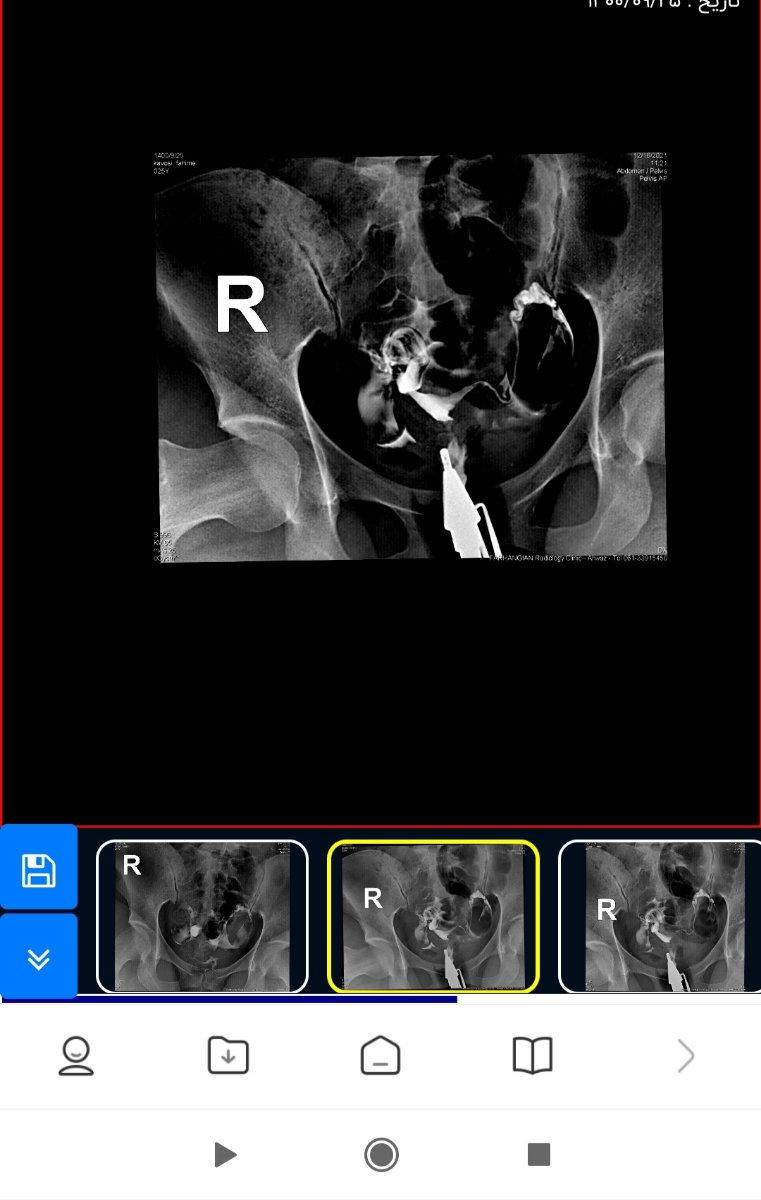

جان دلم نتیجه عکس رنگی از رحم طبیعی و بدون مشکل بوده و خوشبختانه لوله ها باز هستند. تبریک می گویم از این بابت هیچ مشکلی وجود ندارد💜

یعنی ماده وارد لگن شده و لوله ها بازن